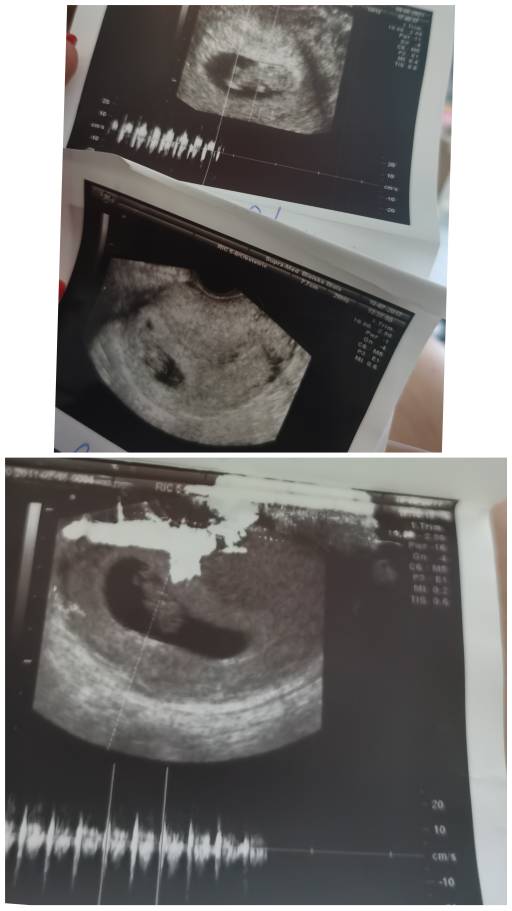

Cześć dziewczyny. Witam się z Wami. Jestem w trzeciej ciąży. Na początku było dużo obaw, nadal są, ale im ciąża wyższa tym ma się więcej nadziei, że będzie wszystko ok. Jestem mamą dwóch chłopców, teraz trzecia ciąża i zastanawiam się czy w brzuszku mieszka trzeci chłopczyk, czy może dziewczynka. Dzisiaj porównywałam sobie układ dzieci w brzuszku i zastanawiam się czy on może mieć wpływ na płeć. Zobaczcie same. Trzeci bobo też ma taki sam uklad, czyli główka z lewej strony, pupka z prawej. Mamy które mają kolejną ciążę może podpowiecie czy u Was się to sprawdziło. Czekam na moją upragnioną perełkę, chociaż to dopiero 10 tydzień to już się jej nie mogę doczekać. Pozdrawiam Was mamusie [emoji4]

Hej ja właśnie porownalam zdjęcia z tego samego okresu mniej więcej.. Na pierwszym są trzy ciąże, pierwsza od góry, obecnie a dwie pozostałe to moje córeczki, na drugim zdjęciu na górze obecnie na dole jedna córka.. Chyba ułożenie jest odwrotne ale nie wiem czy teoria się sprawdzi i będzie inna płec [emoji6] mam 3 córki i oczywiście gdyby był syn to byłoby spełnienie marzeń [emoji3590] w każdym bądź razie ja nastawiam się na córeczkę żeby nie mieć jakiegoś zawodu później [emoji6]

CollageMaker_20210615_084816660.jpeg

CollageMaker_20210615_084906247.jpeg